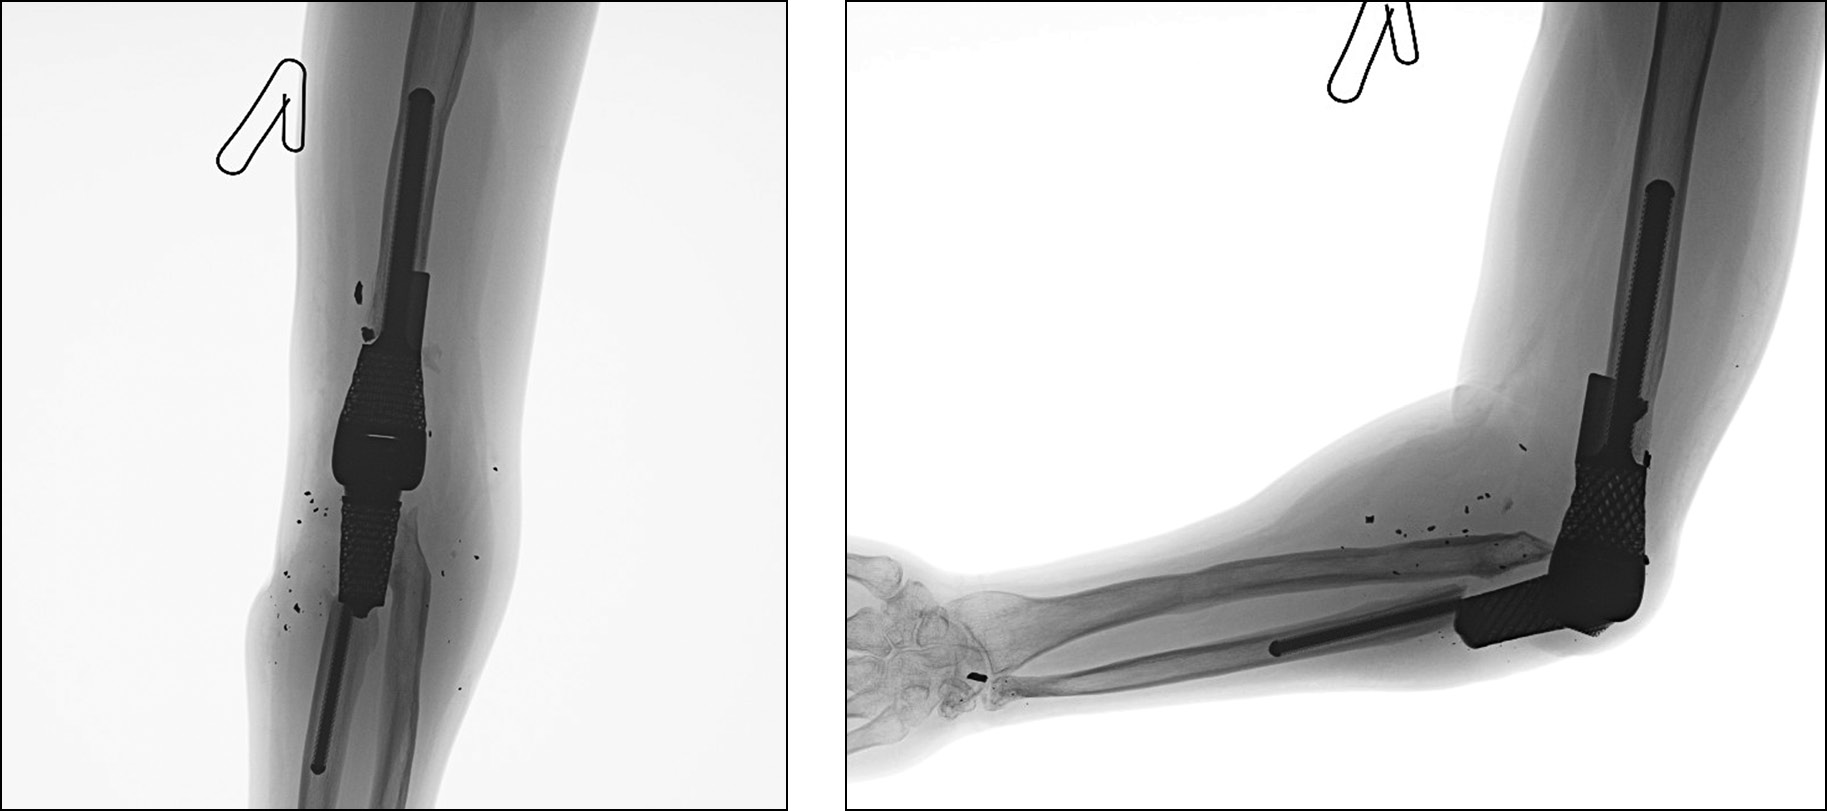

Послеоперационный период протекал без особенностей, выполнен рентген-контроль (рис. 16). Рана зажила первичным натяжением без признаков воспалительной реакции. Гипсовая иммобилизация снята через 4 недели с момента операции. После окончания срока иммобилизации начат курс ЛФК с целью восстановления амплитуды движений в локтевом суставе, увеличения тонуса мышц плеча.

Рис. 16. Пациент Д. Рентгенологический контроль после оперативного вмешательства: а — передне-задняя проекция, b — боковая проекция.

Fig. 16. Patient D. X-ray control after surgery: a — anterior-posterior projection, b — lateral projection.

Через 3 месяца болевых ощущений нет, отмечаются парестезии, незначительное ограничение амплитуды движения в области IV, V пальцев правой кисти. Результаты по шкалам Quick DASH, Oxford Elbow Score — 45 и 84 балла соответственно. Амплитуда движений в правом локтевом суставе: сгибание — 45 градусов, разгибание — 180 градусов, пронация — 90 градусов, супинация — 60 градусов (рис. 17, 18).